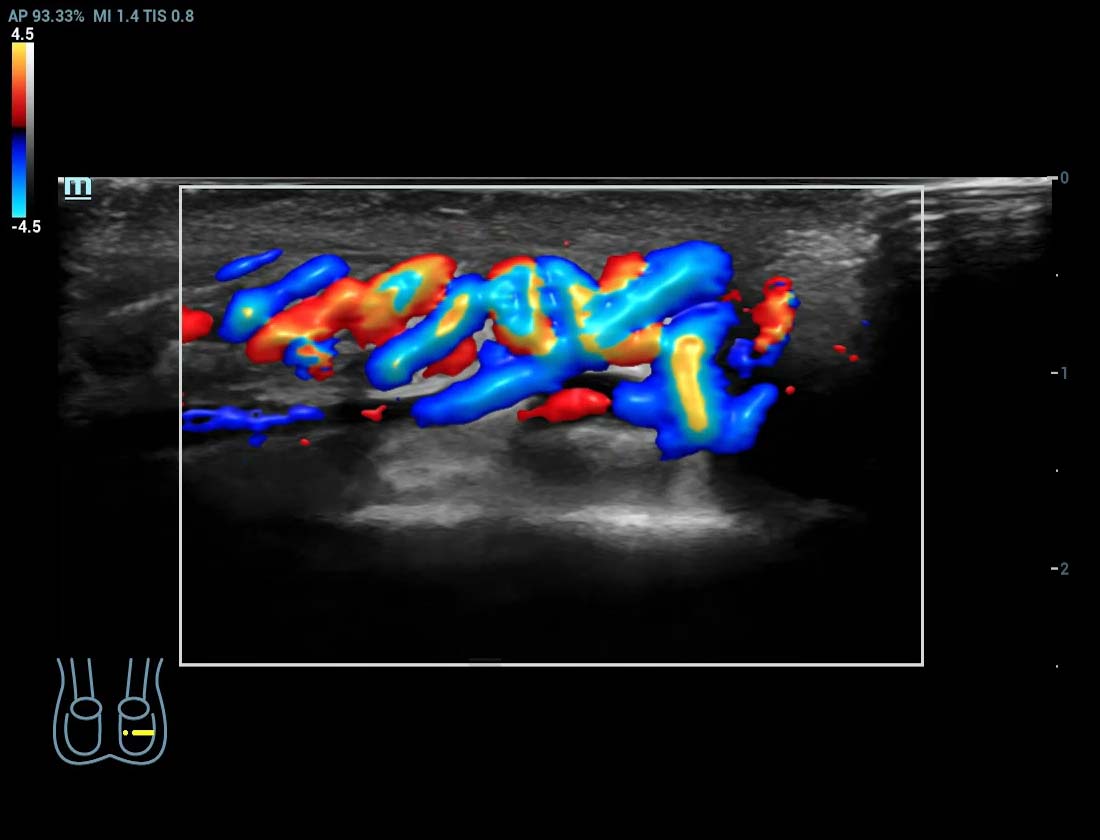

Ultra-micro-angiografie

Breng kleurendoppler op een hoger niveau

Ultra-Micro-angiografie (UMA)

UMA verbetert het diagnostische vertrouwen door de zichtbaarheid van de bloedstromen uit te breiden tot op het kleinste vaatniveau, met een superieure gevoeligheid en resolutie van de bloedstroom.

Varicocele beglazing

Varicocele beglazing sUMA